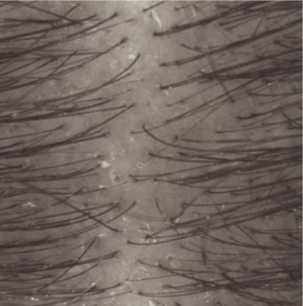

Résultats d'efficacité

Prurit dès les 1ères applications (2)

Induration à 1 mois (3)

(1) Etude clinique auprès de 54 sujets présentant un psoriasis du cuir chevelu léger à modéré. Phase d’attaque de 4 semaines : 3 shampoings par semaine.

(2) Évaluation par le sujet de l’intensité du prurit à J8.

(3) Évaluation clinique de l’induration des plaques à J29.